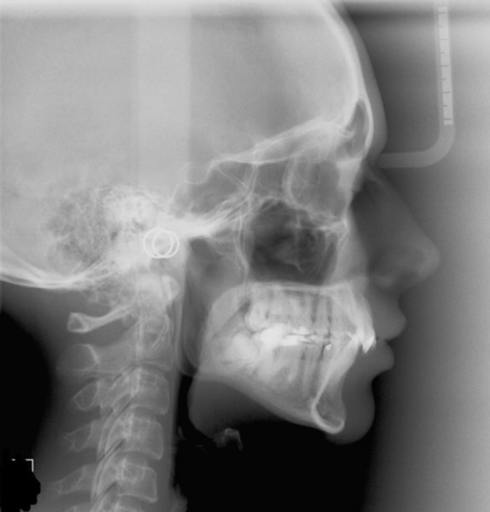

10 mm Overbite - Orthognathic Surgery

Disclaimer: Please do not post my email address, name etc. I have a 10mm overbite with some crowding. I am currently 15y/o without any sort of orthognathic treatment. I was told by the orthodontist that my sister and brother go to that if i wanted to get rid of my overbite I would need to get surgery (They didn't specify what kind of surgery e.g. double jaw etc) I heard that before you get the surgery you would need to have your wisdom teeth removed. Is this true? (I was not told this by my Orthodontist). None of my wisdom teeth have come out yet. Is it even possible to get your wisdom teeth extracted when they haven't come out yet ? Some other information: I was told that along with the surgery I will need to also get 4 teeth pulled out, braces. etc.